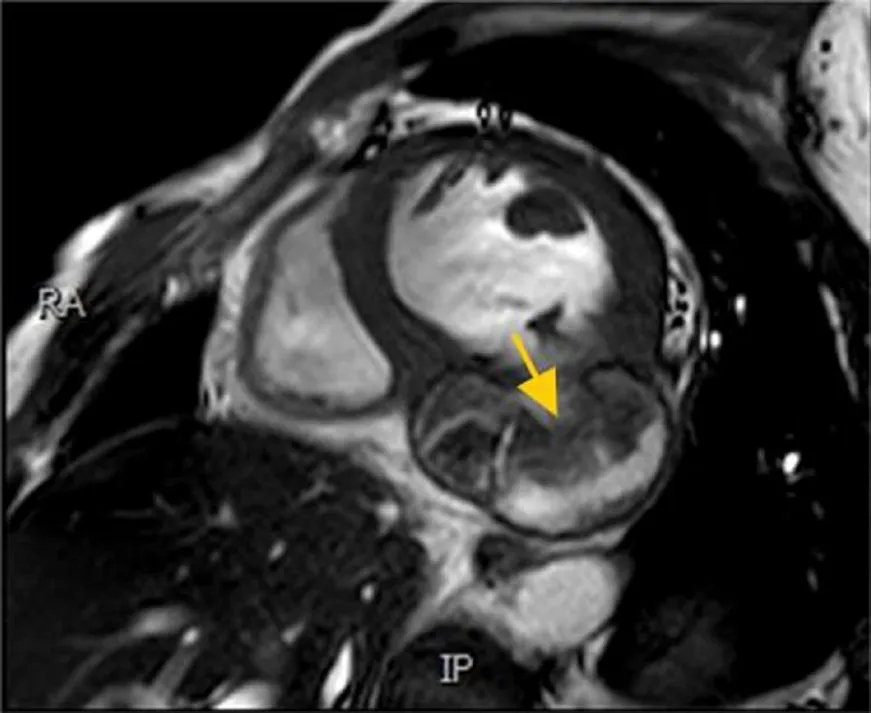

CMR显示基底部下壁、基底部下侧壁、中部下壁和中部下侧壁节段变薄和运动障碍,伴有相应心室壁膨出。此外,注意到周围心包明显延迟强化以及膨出腔内广泛血栓形成。然而,冠状动脉造影显示动脉无阻塞,左前降支和左回旋支狭窄20%至30%,右冠状动脉狭窄30%至40%。尽管心室造影有助于诊断LVP,但因存在完全破裂和栓塞的风险,操作需谨慎[1]。

图3:CMR(短轴)灌注扫描显示中部下壁和下侧壁节段变薄及相应心室壁膨出(箭头)